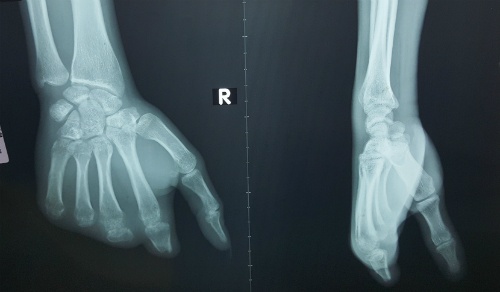

Tai nạn xảy ra khi bé trai 11 tuổi bổ bưởi. Sau tiếng kêu hoảng hốt, bé được người nhà khẩn cấp đưa tới viện.